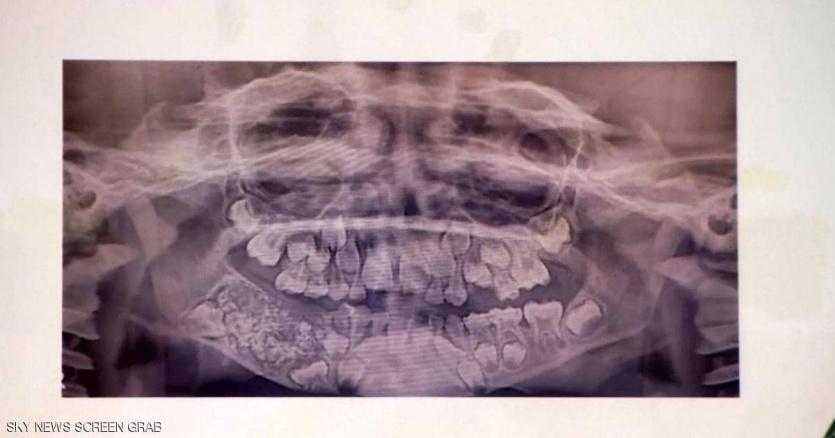

صورة اشعة لاسنان الطفل

أعلن أطباء في الهند، اقتلاعهم لـ526 سنا وضرسا من فم طفل عمره 7 سنوات، يعاني من حالة طبية غير عادية.

ويعاني الطفل من ورم في الجانب الأيمن من الفك السفلي له منذ أن كان عمره 3 سنوات.

وأظهر فحص طبي أجراه جراحون وجود نمو كبير يحتوي على هياكل صلبة متعددة في الفك.

وقال الأطباء إن هذه حالة طبية فريدة من نوعها. ووصفت النادرة بأنها "ورم مركب بالأسنان".